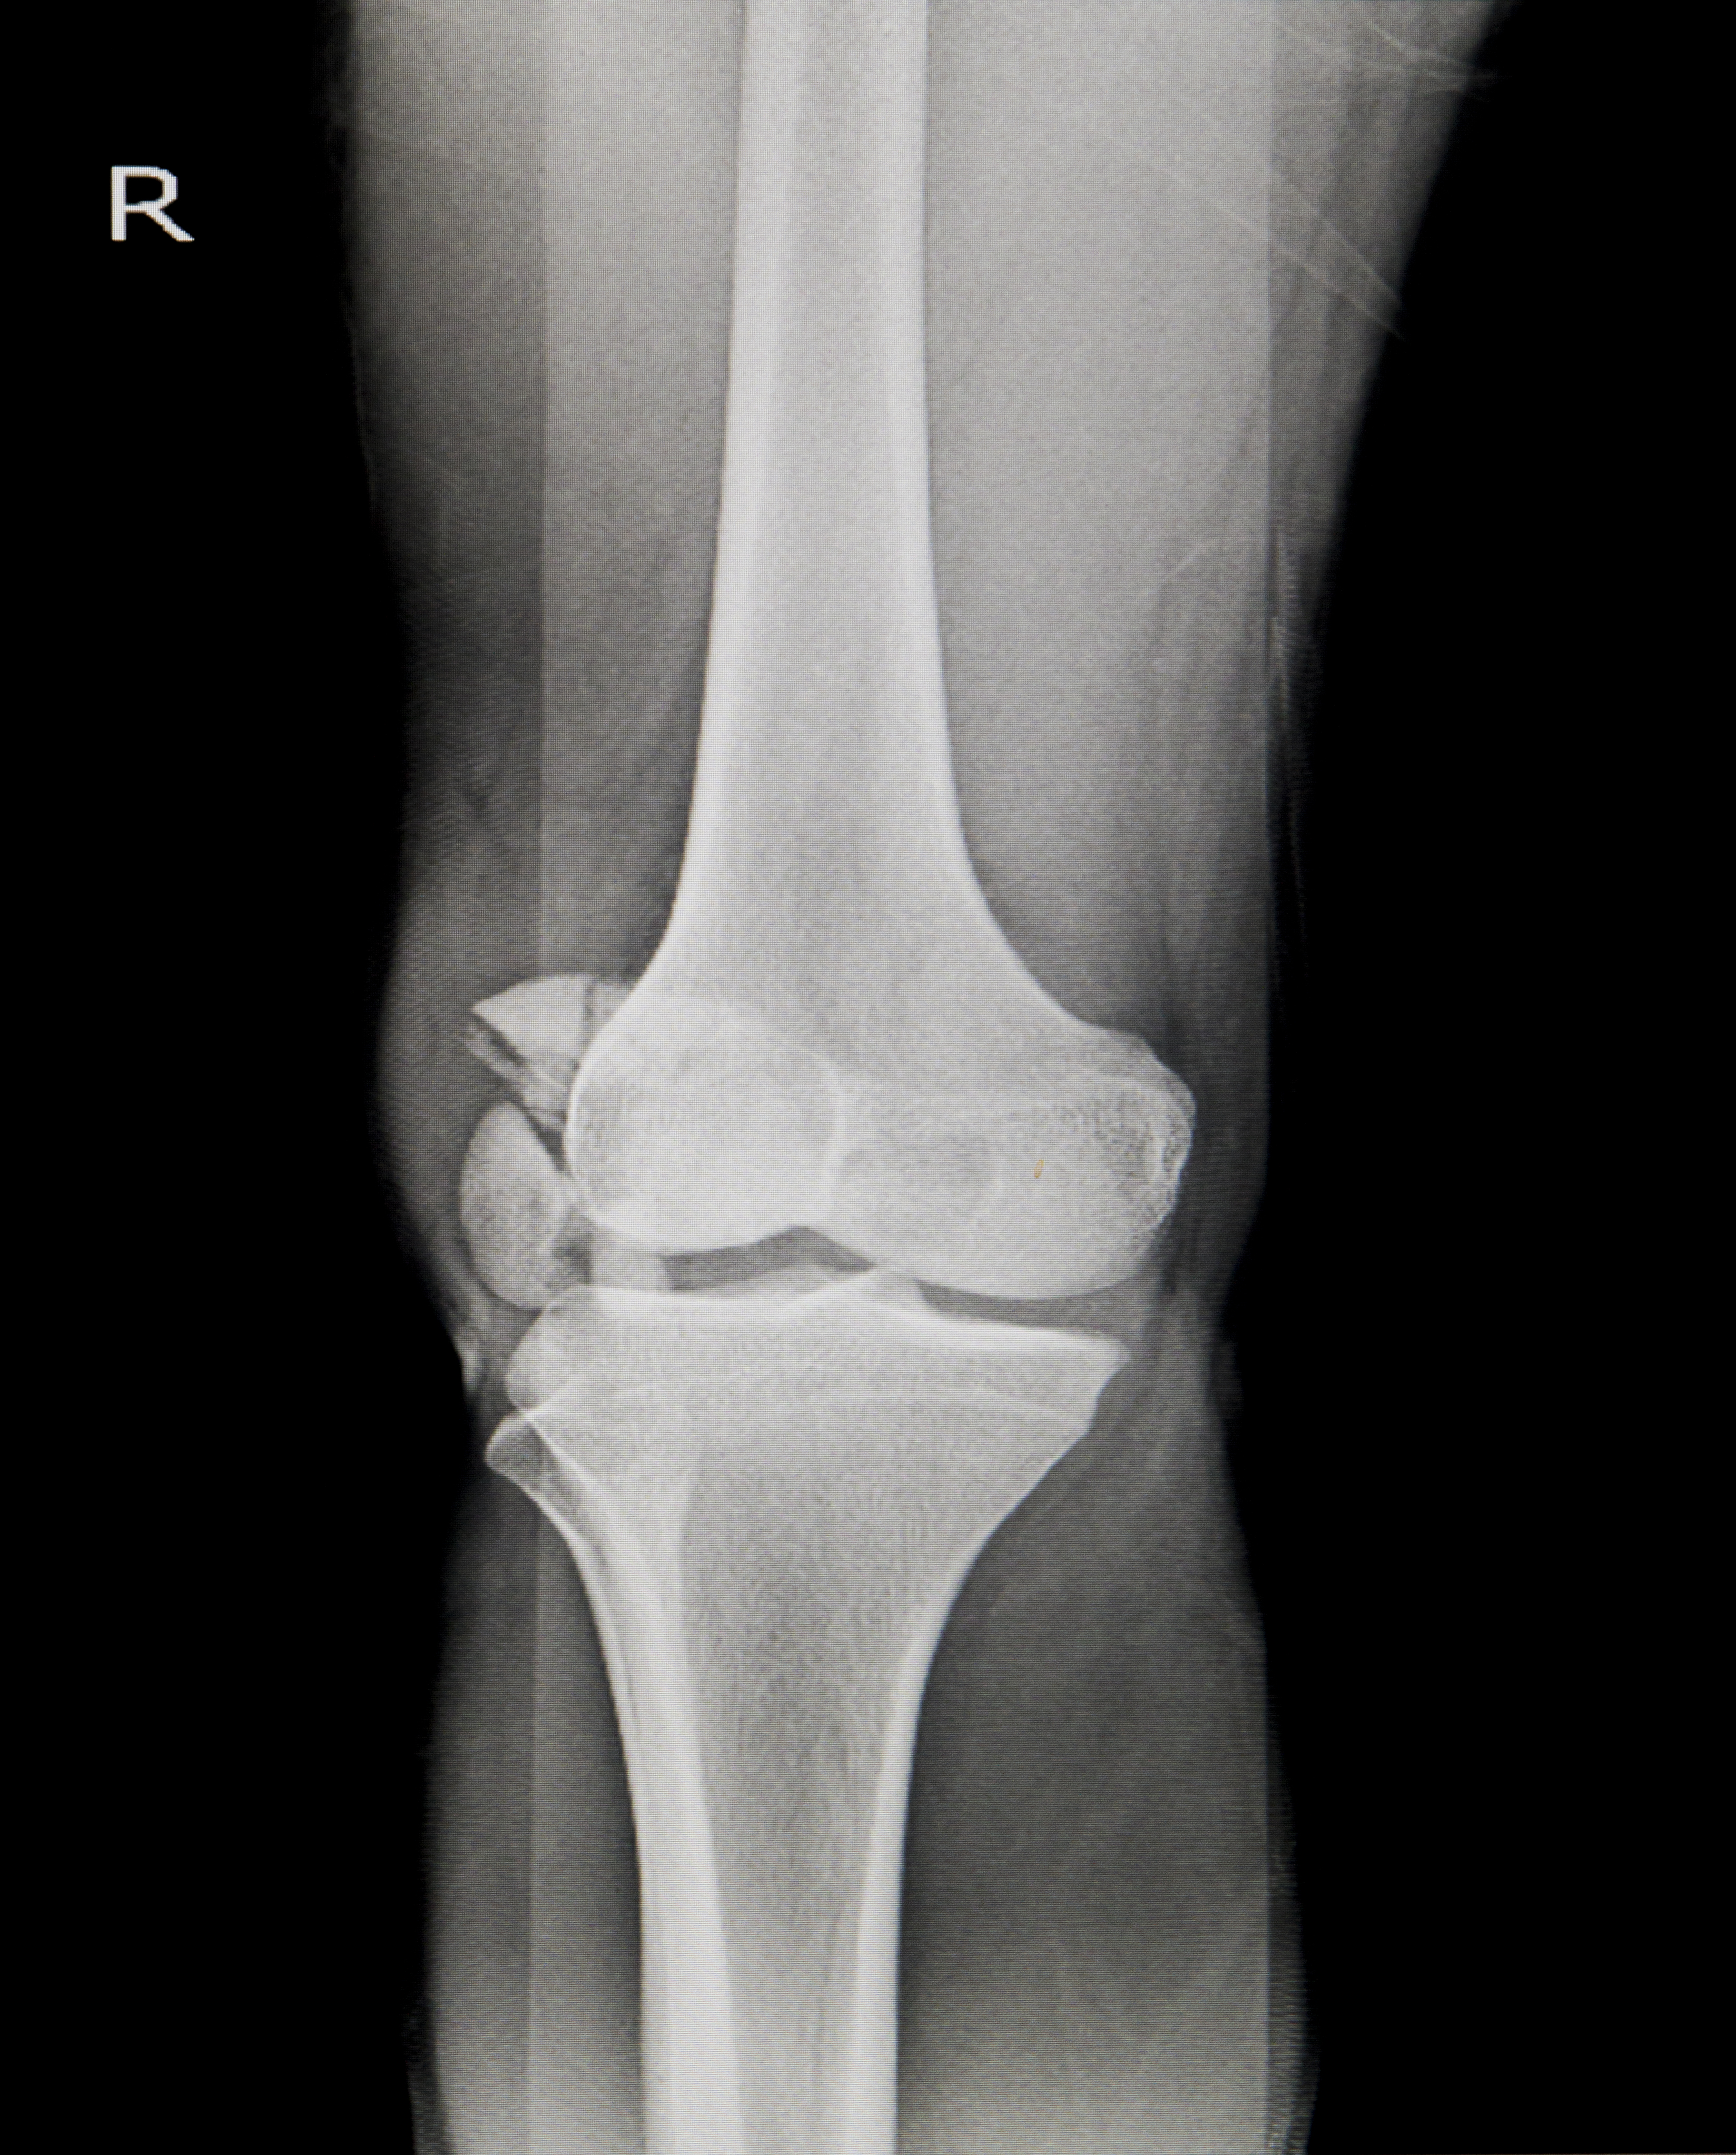

O profissional em ortopedia é responsável por realizar consultas, solicitar exames, realizar diagnósticos, indicar tratamentos, realizar cirurgias, dentre outros. As principais doenças tratadas pela ortopedia são: hérnia de disco, lombalgia, artrose, problemas de crescimento, joanete, bursite, pé diabético, ruptura de ligamentos, lesões dos meniscos, entorses, fascite plantar, tendinite, síndrome do canal cárpico etc. Há também ortopedistas que se especializam em uma parte específica do corpo como punhos e mãos, joelhos, coluna e outros que tratam problemas congênitos como disfunções, deformidades ou sequelas de acidentes.